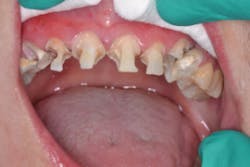

I knew Sarah when she was well and could smile at the world. Then, when the painful loss of a loved one dismantled her life, having no safety net or support, depression set in. Later, substance abuse took over, and eventually Sarah hit rock bottom. Thankfully, a local family took her in, and she is reclaiming her life. But her teeth and smile were devastated (figures 1 and 2).

Wednesday is sedation day in our office, It's one of my favorite days—one patient and all the time I want to care for that one person. Using 3.5x loupes, caries detecting solution, and slow-speed excavation, we teased out massive amounts of decay throughout the arch with complete pulpal communication in teeth Nos. 6, 10, and 11 (figure 4). We were prepared for pulpal involvement and the possibility that multiple teeth might require root canal treatment on the fly. I immediately performed same-day root canals on the three teeth (figure 5).